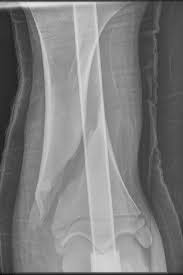

犬ではこれを適用できる骨が限られていますが、大腿骨と橈骨の横骨折に対して、大腿骨の外側面(大腿骨頸の反対側)または橈骨の前内側面に装着します。

上腕骨と脛骨に使用することは少ないが、上腕骨では前面または外側面に、また脛骨の骨折の際にはその内側面に装着することがあります。